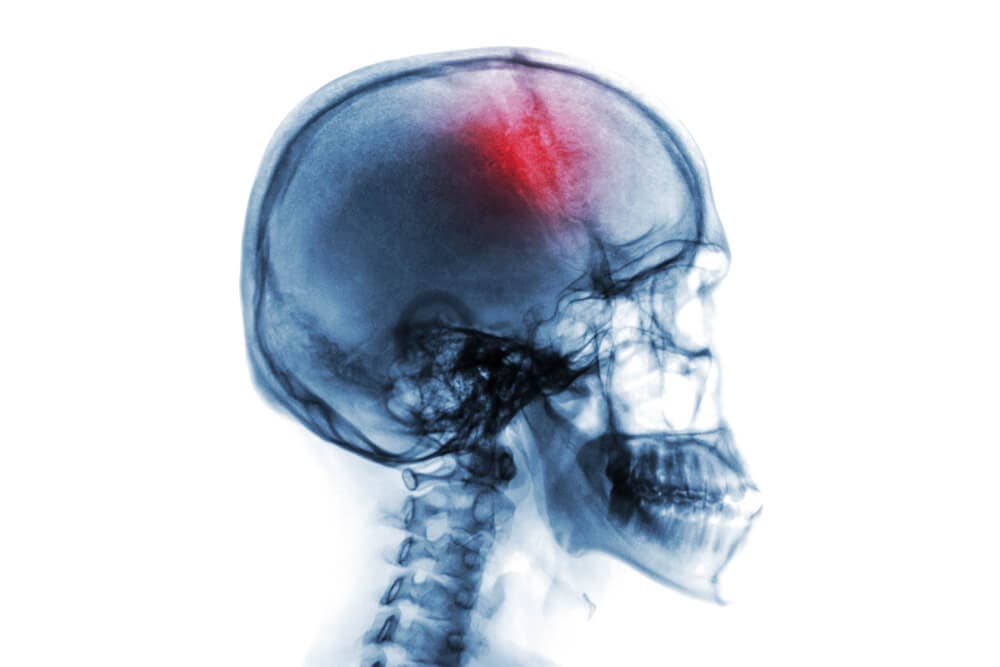

La duramadre y la aracnoides son dos de las tres meninges con que cuenta el ser humano. Las meninges son las estructuras que recubren el sistema nervioso central. Una hemorragia subdural o subaracnoidea se refiere a una hemorragia que ocurre por debajo de cada una de estas dos meninges.

En una hemorragia subdural o subaracnoidea, la circunstancia primera es la salida de sangre de los vasos sanguíneos, que queda almacenada en los espacios entre las meninges. Esto causa daños en el tejido encefálico, generando así diversos cuadros clínicos.

Sin embargo, en función de si la hemorragia es subdural o subaracnoidea, los desencadenantes, el curso de la patología y su clínica serán distintas.